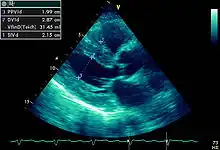

Hypertrophie ventriculaire gauche avec épaississement du muscle cardiaque.